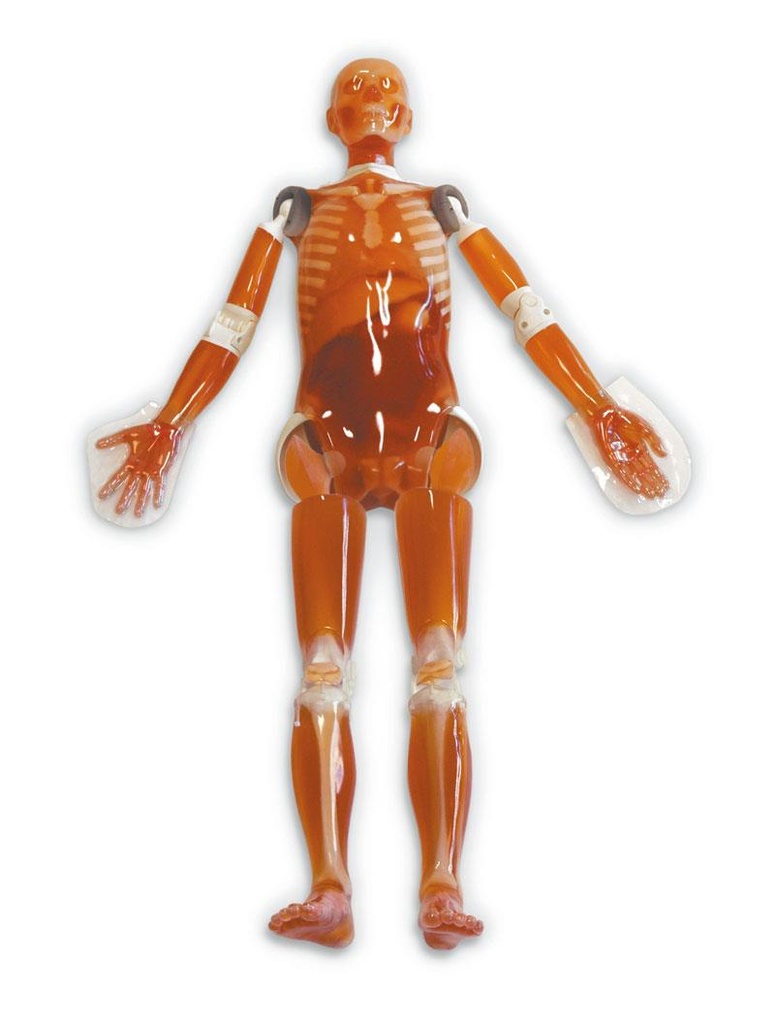

Ein einzigartiges Ganzkörperphantom für CT bietet eine Vielzahl von Ausbildungs- und Forschungsmöglichkeiten. Das Phantom kann auch für normales Röntgen benutzt werden und gibt lebensnahe Bilder. Es benden sich keine Metallteile oder Flüssigkeiten im Phantom. Die wichtigen Gelenke haben eine menschenähnliche Beweglichkeit und erlauben vielfältige Positionen für die Übung. Das Phantom kann in 10 Teile zerlegt werden. Die verbesserten Schultergelenke erlauben es, die Arme nach oben zu bewegen. Die künstlichen Organe sind anatomisch korrekt und haben entsprechende HU-Zahlen.

Patientenpositionierung:

- Schultern rotieren volle 360° in der Sagittalebene, etwa 180° seitwärts.

- Hüftgelenke rotieren vorwärts bis etwa 90°, dann jeweils bis zu 45° auswärts.

- Knie können bis etwa 90° gebeugt werden.

- Ellenbogen beugen sich bis etwa 90°.

- Das Phantom kann auf dem Rücken liegend die Froschbein-Position einnehmen.

- Die Extremitäten und der Kopf können abgenommen werden.

- Die Kopfstütze erlaubt vielfältige Kopfpositionen.

Innere Organe und Strukturen:

- Kopf und Rumpf

- Synthetischer Schädel

- Halswirbel

- Gehirn

- Wirbel

- Schlüsselbeine

- Rippe

- Brustbein

- Schulterblätter

- Beckenknochen

- Oberschenkel

- Lungen mit Pulmonalgefäßen

- Luftröhre

- Leber mit Pfortader und Lebervene

- Bauchspeicheldrüse

- Nieren

- Gallenblase

- Milz

- Aorta

- Vena Cava

- Harnleiter

- Harnblase

- Prostata

- Rektum

- Colon sigmoideum